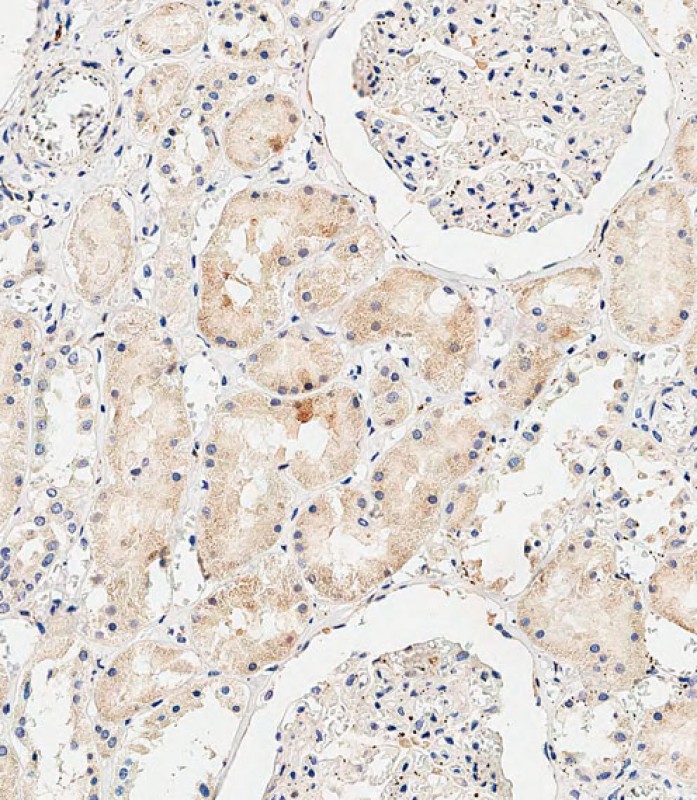

IHC 1/500 Human,Mouse,Rat

COL8A2 antibodies target the alpha-2 chain of collagen type VIII, a short-chain collagen primarily found in basement membranes and extracellular matrices. Encoded by the COL8A2 gene, this protein contributes to tissue structure and cellular adhesion. COL8A2 is notably expressed in vascular endothelial cells, the eye (particularly the corneal endothelium), and certain epithelial tissues. Research on COL8A2 antibodies has been driven by its association with Fuchs' endothelial corneal dystrophy (FECD), a genetic disorder causing corneal degeneration. Specific mutations in COL8A2. such as the L450W variant, are linked to early-onset FECD, making these antibodies valuable for studying disease mechanisms. Additionally, COL8A2 is implicated in angiogenesis and tumor microenvironment regulation, with studies suggesting its role in modulating blood vessel stability in cancers. Antibodies against COL8A2 are used in techniques like immunohistochemistry, Western blotting, and immunofluorescence to localize and quantify its expression in tissues or cell cultures. They also aid in exploring COL8A2's interactions with signaling molecules involved in cell proliferation and matrix remodeling. While most applications remain research-focused, potential clinical uses include diagnostic tools for corneal dystrophies or biomarkers for vascular abnormalities. However, standardization of antibody specificity and validation across species and sample types remains a challenge in translating these findings into therapeutic or diagnostic advancements.